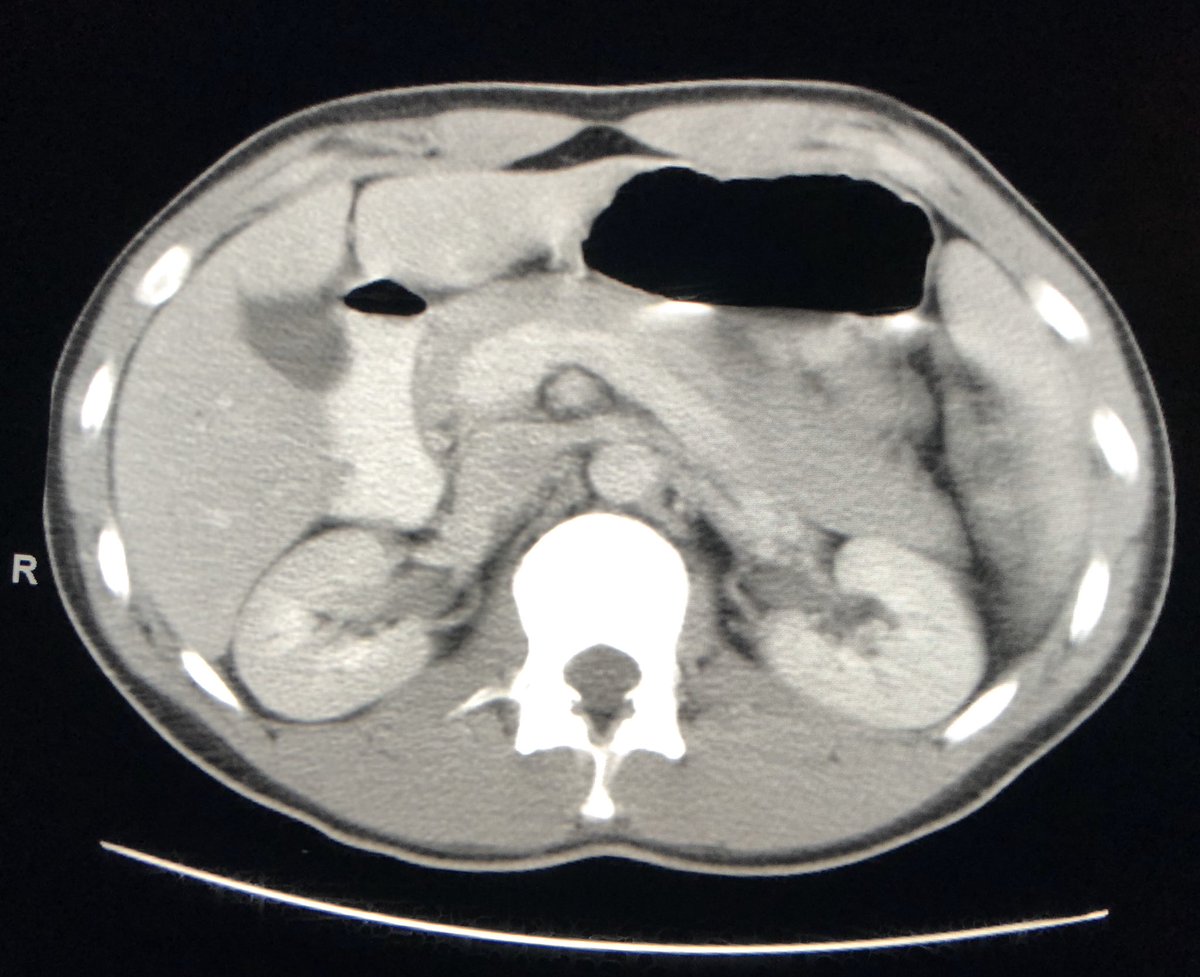

Bleeding hepatic adenoma. The things that just walk into your emergency department....pic.twitter.com/rnU8L54oSk

Hvala. Twitter će to iskoristiti za poboljšanje vaše vremenske crte. PoništiPoništi -